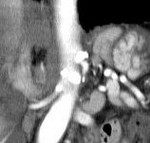

[画像診断]正中弓状靱帯について 2010-06-09

[画像診断]正中弓状靱帯について